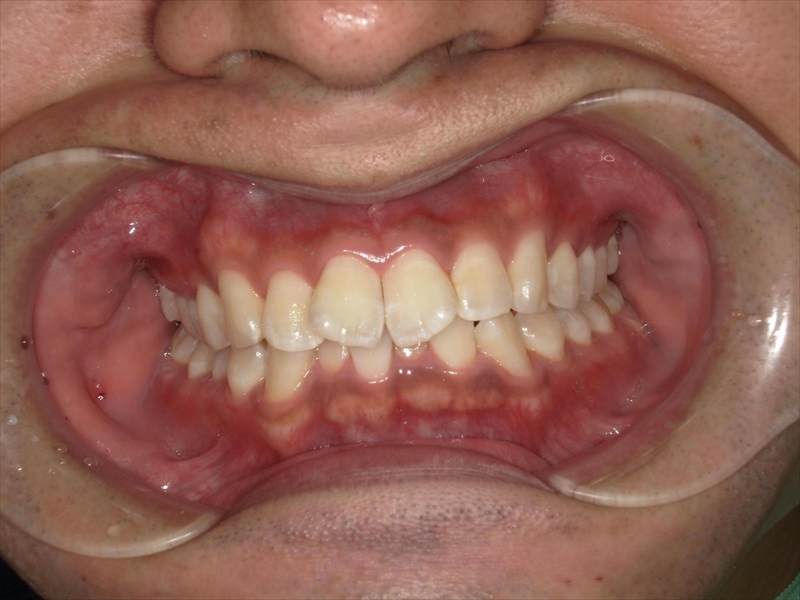

【大人矯正治療例】前歯のV字状の捻じれと出っ歯、叢生、過蓋咬合をインビザラインできれいな歯並びに

- 上あごの前歯がV字状の出っ歯

- 下あごの前歯もがたついている(叢生)

- 上あごに対して下あごがかなり小さい(過蓋咬合)

治療前後 写真